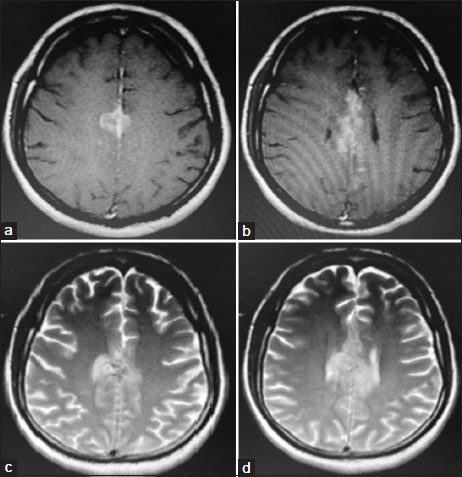

On evaluation, magnetic resonance imaging brain and thoraco-lumbo-sacral spine showed heterogeneous hyperintense lesion [Figure 1] in the parasagittal region and patchy dural enhancement in the cervicodorsal region. Videostroboscopy showed left vocal cord palsy. Fluorodeoxyglucose PET-CT ruled out disease at other sites. These findings pointed to bulbar palsy as a possible cause of his hoarseness of voice and dysphagia. The bulbar palsy was likely a result of leptomeningeal disease. CSF was planned to confirm the same. CSF showed atypical cells, which were suspicious of malignancy, CSF protein was 266.7 mg/dl, and glucose was 29.4 mg/dl. To confirm the diagnosis and primary, IHC markers were done on cell blocks from CSF [Figure 2]. Cell block from CSF showed malignant cell clusters in [Figure 2]a and [Figure 2]b. CK7-positive cells are in [Figure 2]c and MUC-1 (Mucin-1, cell surface associated protein (clone MMAB,BioSB))-positive cells in [Figure 2]d. Cells were negative for CK20 and CDX2. Diagnosis of metastatic adenocarcinoma was confirmed on CSF with strong MUC1 staining favoring pancreatobiliary origin. For dysphagia, nasogastric feeding was started. Intrathecal chemotherapy (IT) was given with methotrexate and hydrocortisone weekly. Post 3 weeks of IT chemotherapy, the patient had symptomatically improved. However, the patient succumbed to chest infection in April 2020.

| Figure. 1(a and b) T1-weighted images showing intermediate signal lesions. (c and d) T2-weighted images showing hyperintense lesions